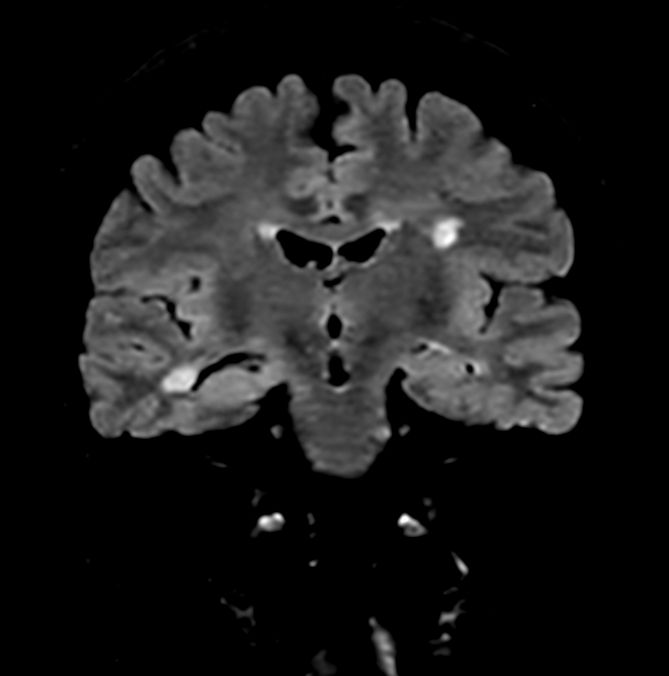

Axial DWI b1000